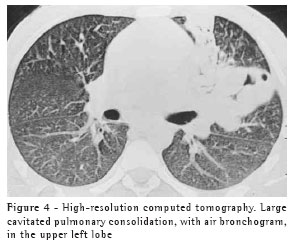

The most frequent finding in the imaging, present in the seven patients, was ill-defined consolidation (Figures 1, 2, 3 and 4). Five of patients presented air bronchogram, principally at the periphery of the lesion. In three cases, the consolidation was organized in the form of a mass. In six of the seven patients, irregular areas of cavitation were observed within the consolidations. Multiple cavitations were seen in five patients, and a singular cavitation was observed in one patient. In the patient presenting no cavitation, there were hypodense areas suggestive of necrosis (Figure 5). Only one of the patients presented air-fluid levels within the cavities.

Cavitated lesions predominated in the upper lobes, four in the right lobe and one in the left lobe. In one patient, the middle lobe was also affected. In two cases, such lesions occurred in the lower lobes, one in the right lobe and one in the left lobe. In four cases, the lesions affected only the lobes mentioned above and were therefore unilateral. In the remaining three cases, the contralateral lung was also affected, albeit to a lesser degree. In one case, there was also relatively thin-walled, multiloculated cavitation, without an air-fluid level, in the middle lobe.

In our study, the principal pattern of pulmonary involvement was air bronchogram and cavitation, which was present in six patients. There were multiple cavitations in five cases and a singular cavitation in one. The consolidations were large and had irregular contours. The air bronchograms were located in the peripheral portions of the lesions. The pulmonary lobe most frequently involved was the upper right lobe, which was affected in four patients. Most of the case review studies confirm these findings.(2,5) Some studies have reported that, although cavitation might not be present at the time of diagnosis, it develops over the course of the disease.(4) In the sample evaluated in the present study, air-fluid levels within the cavitations were seen in only one patient.